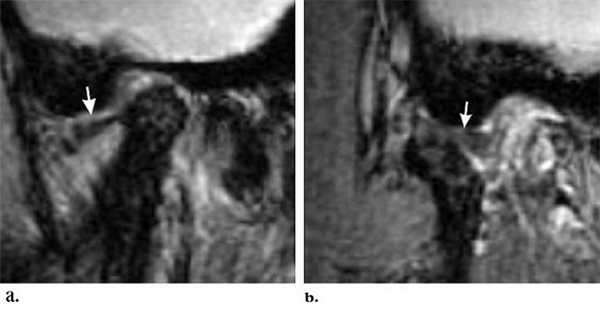

«Застрявший» диск. PD sag изображения с открытым (А) и закрытым (Б) ртом - задний край диска (стрелка) остается в нижнечелюстной ямке височной кости. По этой причине открывание рта сильно ограничено. Вероятная причина - образование спаек.